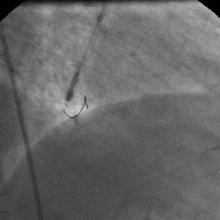

The left system was engaged with XB 3.5 guiding catheter through the femoral route. With the help of a 1.1x1.5mm CTO balloon, we directed a Shinobi guidewire towards the ostial LAD lesion (Figure 4). After making sure that the guidewire was pointing towards the CTO with its tip at the CTO lesion, we used the torquer to gently twirl the guidewire without forcing or overly manipulating it and allowed the guidewire to find its own way through the CTO by patiently twirling it at the lesion site. Within a few minutes, the guidewire jumped through the CTO lesion (Figure 5) and then through the lesion with the help of the CTO balloon (Figure 6). The path was first confirmed by engaging the RCA from the radial approach and injecting dye into the RCA (Figure 7). The CTO was then predilated with a 2.0x30mm Sapphire balloon (Figure 8 and Figure 9) and stented it with a 3.0x36mm DES (Figure 10 and Figure 11). Later the RCA was engaged with a JR 3.5 guiding catheter. A Cougar guidewire crossed the RCA lesion that was directly stented with a 3.0x13mm BMS (Figure 12 and Figure 13).